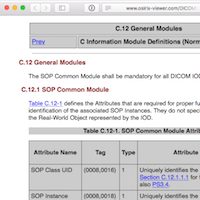

DICOM Standard 2016

DICOM Standard 2016